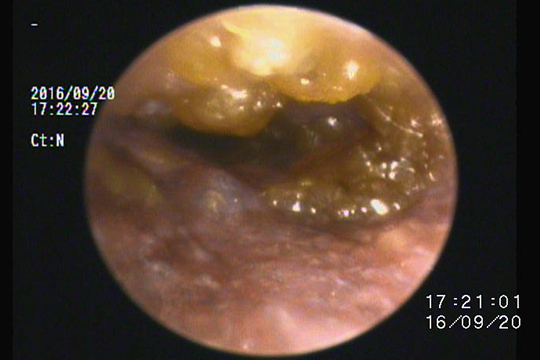

ベトベトした耳垢です。

このような場合、耐性菌などの感染症が起こっている場合と、鼓膜が破れて中耳炎になっている場合が考えられます。

鼓膜の確認と細菌培養、場合により鼓室内洗浄などを行います。